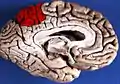

Precuneus of left cerebral hemisphere (shown in red).

Medial surface of left cerebral hemisphere. (Precuneus colored in red.)